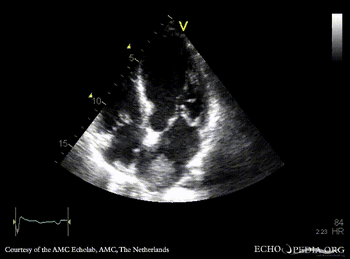

Tumor growing into the left atrium

Courtesy of: AMC Echolab, AMC, The Netherlands

A4CH: tumor growing from pulmonary vein into the left atrium in patient with lung carcinoma A4CH, zoom